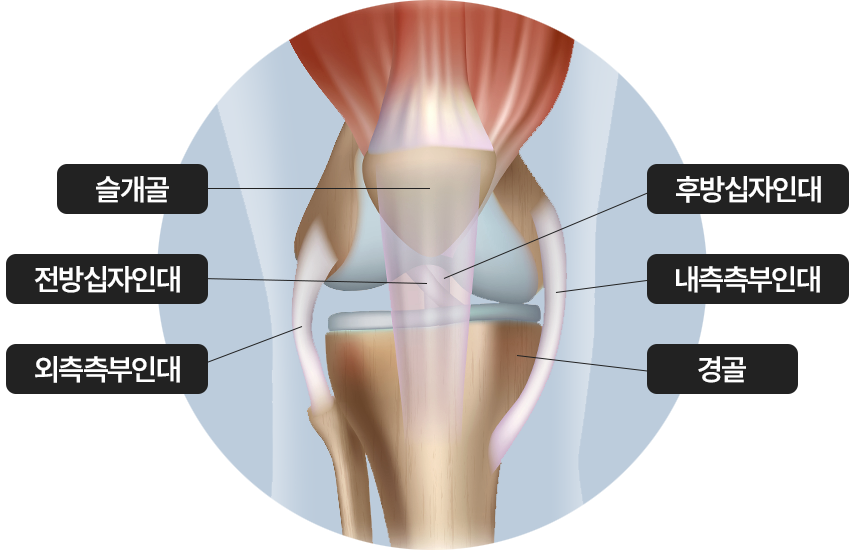

무릎관절의 큰 충격, 과도한 회전, 갑작스러운 움직임으로 인해 전후방 십자인대나

측부 인대 손상

무릎관절의 인대, 힘줄, 연골, 반월상 연골판, 뼈 등

세부 조직의 손상과 통증의 정도, 유발 요인이 다르므로